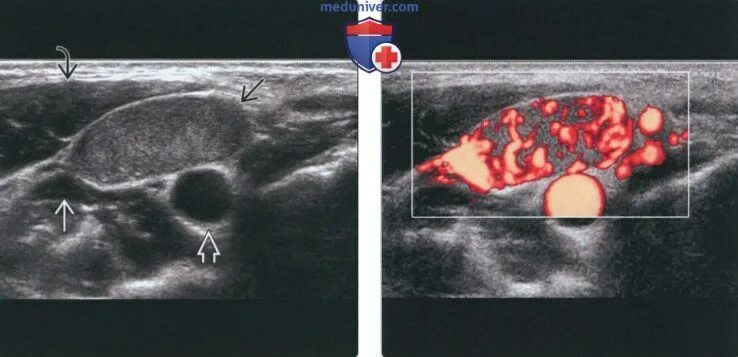

Какой лимфоузел при раке молочной железы